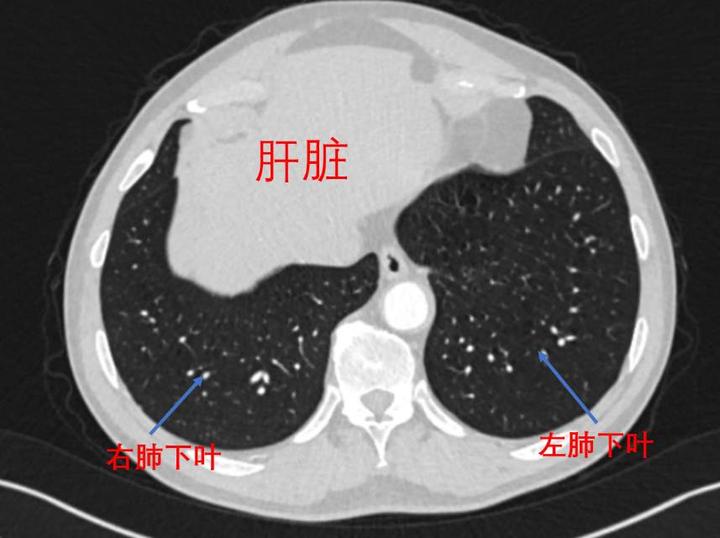

肺下叶位置图

肺部的基本解剖知识(如此详细的肺部影像解剖)(8)